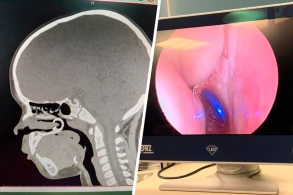

Rusiyanın Çuvaşiyanın Respublika Uşaq Xəstəxanasında həkimlər burnuna pirsinq sırğa taxmaq qərarına gələn və onu nəfəslə çəkən balaca qızı xilas ediblər.

Yad cisim nazofarenksə düşüb, müayinə zamanı həkimlər sırğa aşkarlayıb endoskopik yolla çıxarıblar, heç bir cərrahi müdaxilə tələb olunmayıb.

Həkimlər xatırladıblar ki, uşaq yad cismi udubsa və ya tənəffüs edibsə, heç bir halda onu özünüz çıxarmağa çalışmayın, cisim tənəffüs yollarına daxil olarsa, təcili yardım çağırmalısınız, geri dönməz nəticələr mümkündür.